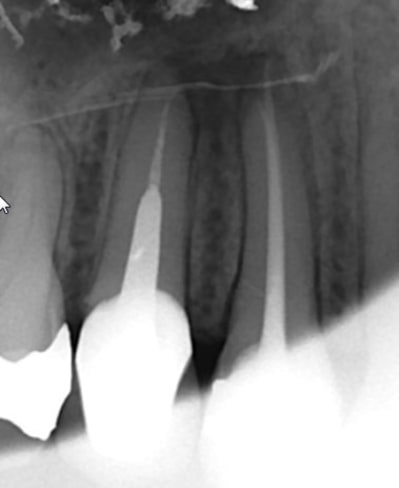

Ci joint un cas vu le 29/04/2014 pour une douleur à la mastication au niveau des prémolaires sup. droites. Douleurs à la percussion au niveau de 14 et 15. Aucune réponse au test thermique au niveau de 14.

Je décide de traiter en 1ère intention la 14 nécrosé. Les symptômes diminuent largement, mais il demeure une zone douloureuse à la palpation au niveau de la table vestibulaire (la lésion est palpable entre les deux racines 14-15).

Le patient pas très sérieux disparait avec sa provisoire durant plus d'un an...

Il refait surface en Août 2015! La lésion est toujours visible à la radio. Le kyste est toujours palpable en vestibulaire. La palpation est toujours douloureuse.

On décide de déposer la couronne et l'ic de la 15, afin de refaire le traitement canalaire des deux dents 14 et 15.

Suite au retraitment de la 15, une fistule apparait en vestibulaire. La radio cône de gutta dans la fistule montre que celui-ci remonte jusqu'à la lésion (peut être plus au niveau de l'apex de la 15?!). Comme le canal V de la 14 n'est pas obturé jusqu'à l'apex je décide de retraiter ce canal...

Patient revu ce matin, la fistule de ne referme toujours pas, et ça gonfle par intermittence selon les dire du patient, mais le cône de gutta ne remonte plus jusqu'au niveau des apex de 14 et 15... (signe de début de guérison?)

Je décide de retraiter la 15, mais cette fois-ci j'obture au MTA + cônes de gutta ; j'ai pas encore de biocéramique... :-(

Un cône beam a été prescrit, et l'étape suivante est la résection apicale si la fistule ne se referme pas la semaie prochaine!